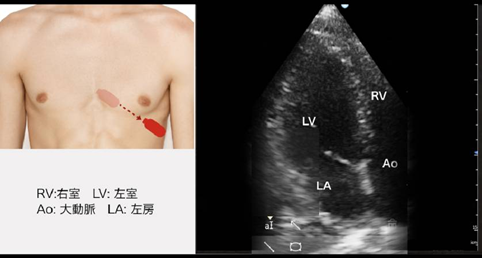

1.傍胸骨長軸像の走査と正常像

【断層法】僧帽弁逸脱 (MVP)、左室壁運動

【Mモード】左房径、左室径、中隔厚、EF、%FS

【カラー】僧帽弁逆流(MR)、大動脈弁逆流(AR)

を評価する

- 左側臥位で、 左腕を拳上させ肋間を広げる、プローベを左傍胸骨におき、 右肩に向ける、高さの目安は、乳頭間または1個上の肋間

- 左室が最大に描出され、 大動脈前壁と心室中隔の高さを合わせる (もしくは大動脈前壁のほうかがやや高くなる断面)→左室が一番長く見え、A弁とM弁が1スライスで表示される

- 断層法の計測は内側から内側→trailing edge to leading edge

▼このビューで計測する項目

- ◎IVSth:thickness of interventricular septum (心室中隔厚拡張期) 7-11mm

IVSthは12mm超えていたら、 「左室肥大あり」と覚える。 左室拡大の鑑別は、 拡張型心筋症、 二次性心筋症 (心臓サルコイドーシスなど)、 虚血性心筋症、 弁膜症性心筋症 (AR、 MR)、 先天性心疾患など - ◎LVDd :left ventricular end-diastolic diameter(左室内径拡張期) 36-52mm

LVDdは男性で55mm、 女性で50mm超えていたら、「左室拡大あり」 と覚える。 左室拡大の鑑別は、 拡張型心筋症、 二次性心筋症(心臓サルコイドーシスなど)、 虚血性心筋症、 弁膜症性心筋症 (AR、 MR)、 先天性心疾患など - LVDs (左室内径収縮期) 22-39mm

- LVPWth (左室下壁厚拡張期) 8-12mm

- AoD (大動脈径) 20-32mm

- ◎LAD (左房径) 27-38mm

LADは40mm超えていたら、 「左房拡大あり」 と覚える。 左房拡大の鑑別は、 心房細動、 MRなど - ◎EF (左室駆出分画) 50-65%→意外と簡単に計測可能!!!

Mモードエコー図による求め方は, 傍胸骨長軸像あるいは短軸像で, 左室最大短径を通るビーム方向での心室中隔左室側心内膜面から, 左室後壁心内膜面までの垂直 (直線) 距離を拡張末期と収縮末期で計測する。

なんと、LVDdとLVDsさえ、わかればすなわちEFが計算できてしまう。

理論式LVEF[%] = ( LVEDV – LVESV ) / LVEDV * 100

計算式として Teichholz 法が一般的である(計算式の詳細は難しいので省略).

この式は拡大し, 球形に近づいた左室にも応用でき, 左室造影で求めた容積と相関がよいとされている. ただし,

心室瘤など左室の形態が回転楕円体から大きくはずれる症例には適応できない. また, 心室壁運動が局所的収縮異

常 (asynergy) を伴う症例にも不適である.